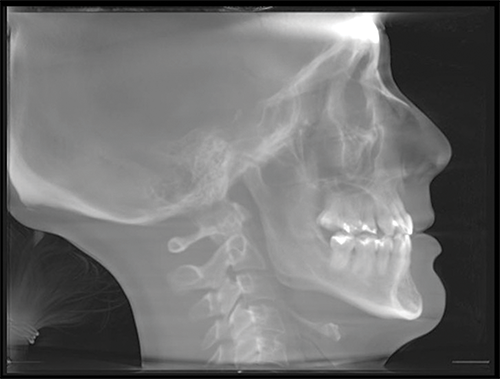

Her chief complaint was related to airway issues, and she sought a nonsurgical remedy (Fig. 3). The bicuspid extractions were erroneously implicated as the cause of her breathing problems. Her general dentist claimed her breathing issues could be nonsurgically corrected with the AGGA by reopening the extraction sites with the intention of creating space for implants, effectively attempting to reverse the extractions and the presumed cause of the airway issues. The patient wore the device for one year, during which time the treating dentist claimed she had achieved 7 mm of forward maxillary bone growth. (Fig. 4)

Ignoring Biological Limitations

Fig. 3: 2013 CBCT-generated lateral cephalogram taken before treatment. Patient-provided scan